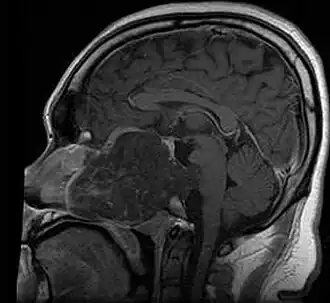

MRI of extensive clival chordoma in 17-year-old male patient, sagittal view. Tumor in the nasopharynx extending from nasal cavity to brainstem posteriorly is clearly visible.